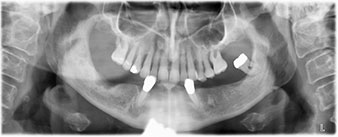

Nach der Zeit, die für die Osseointegration benötigt wird, kann die endgültige Abformung der Implantate erfolgen und entsprechend die endgültige Arbeit angefertigt werden (Abb. 19 und 20). Hier können Behandler und Patient gemeinsam entscheiden, ob diese eine Keramik- oder Kunststoffverblendung, ein Zirkon- oder Metallgerüst bekommen soll. Im vorliegenden Fall hat sich das Team um Dr. Pascu, aufgrund der unklaren Prognose der Oberkieferbezahnung und des elongierten Zahnes 24, für eine Kunststoffverblendung entschieden. Diese ist im Allgemeinen wesentlich einfacher umzustellen und der neuen Situation im Oberkiefer anzupassen.

Osseointegration

Abb. 19

Implantate

Abb. 20